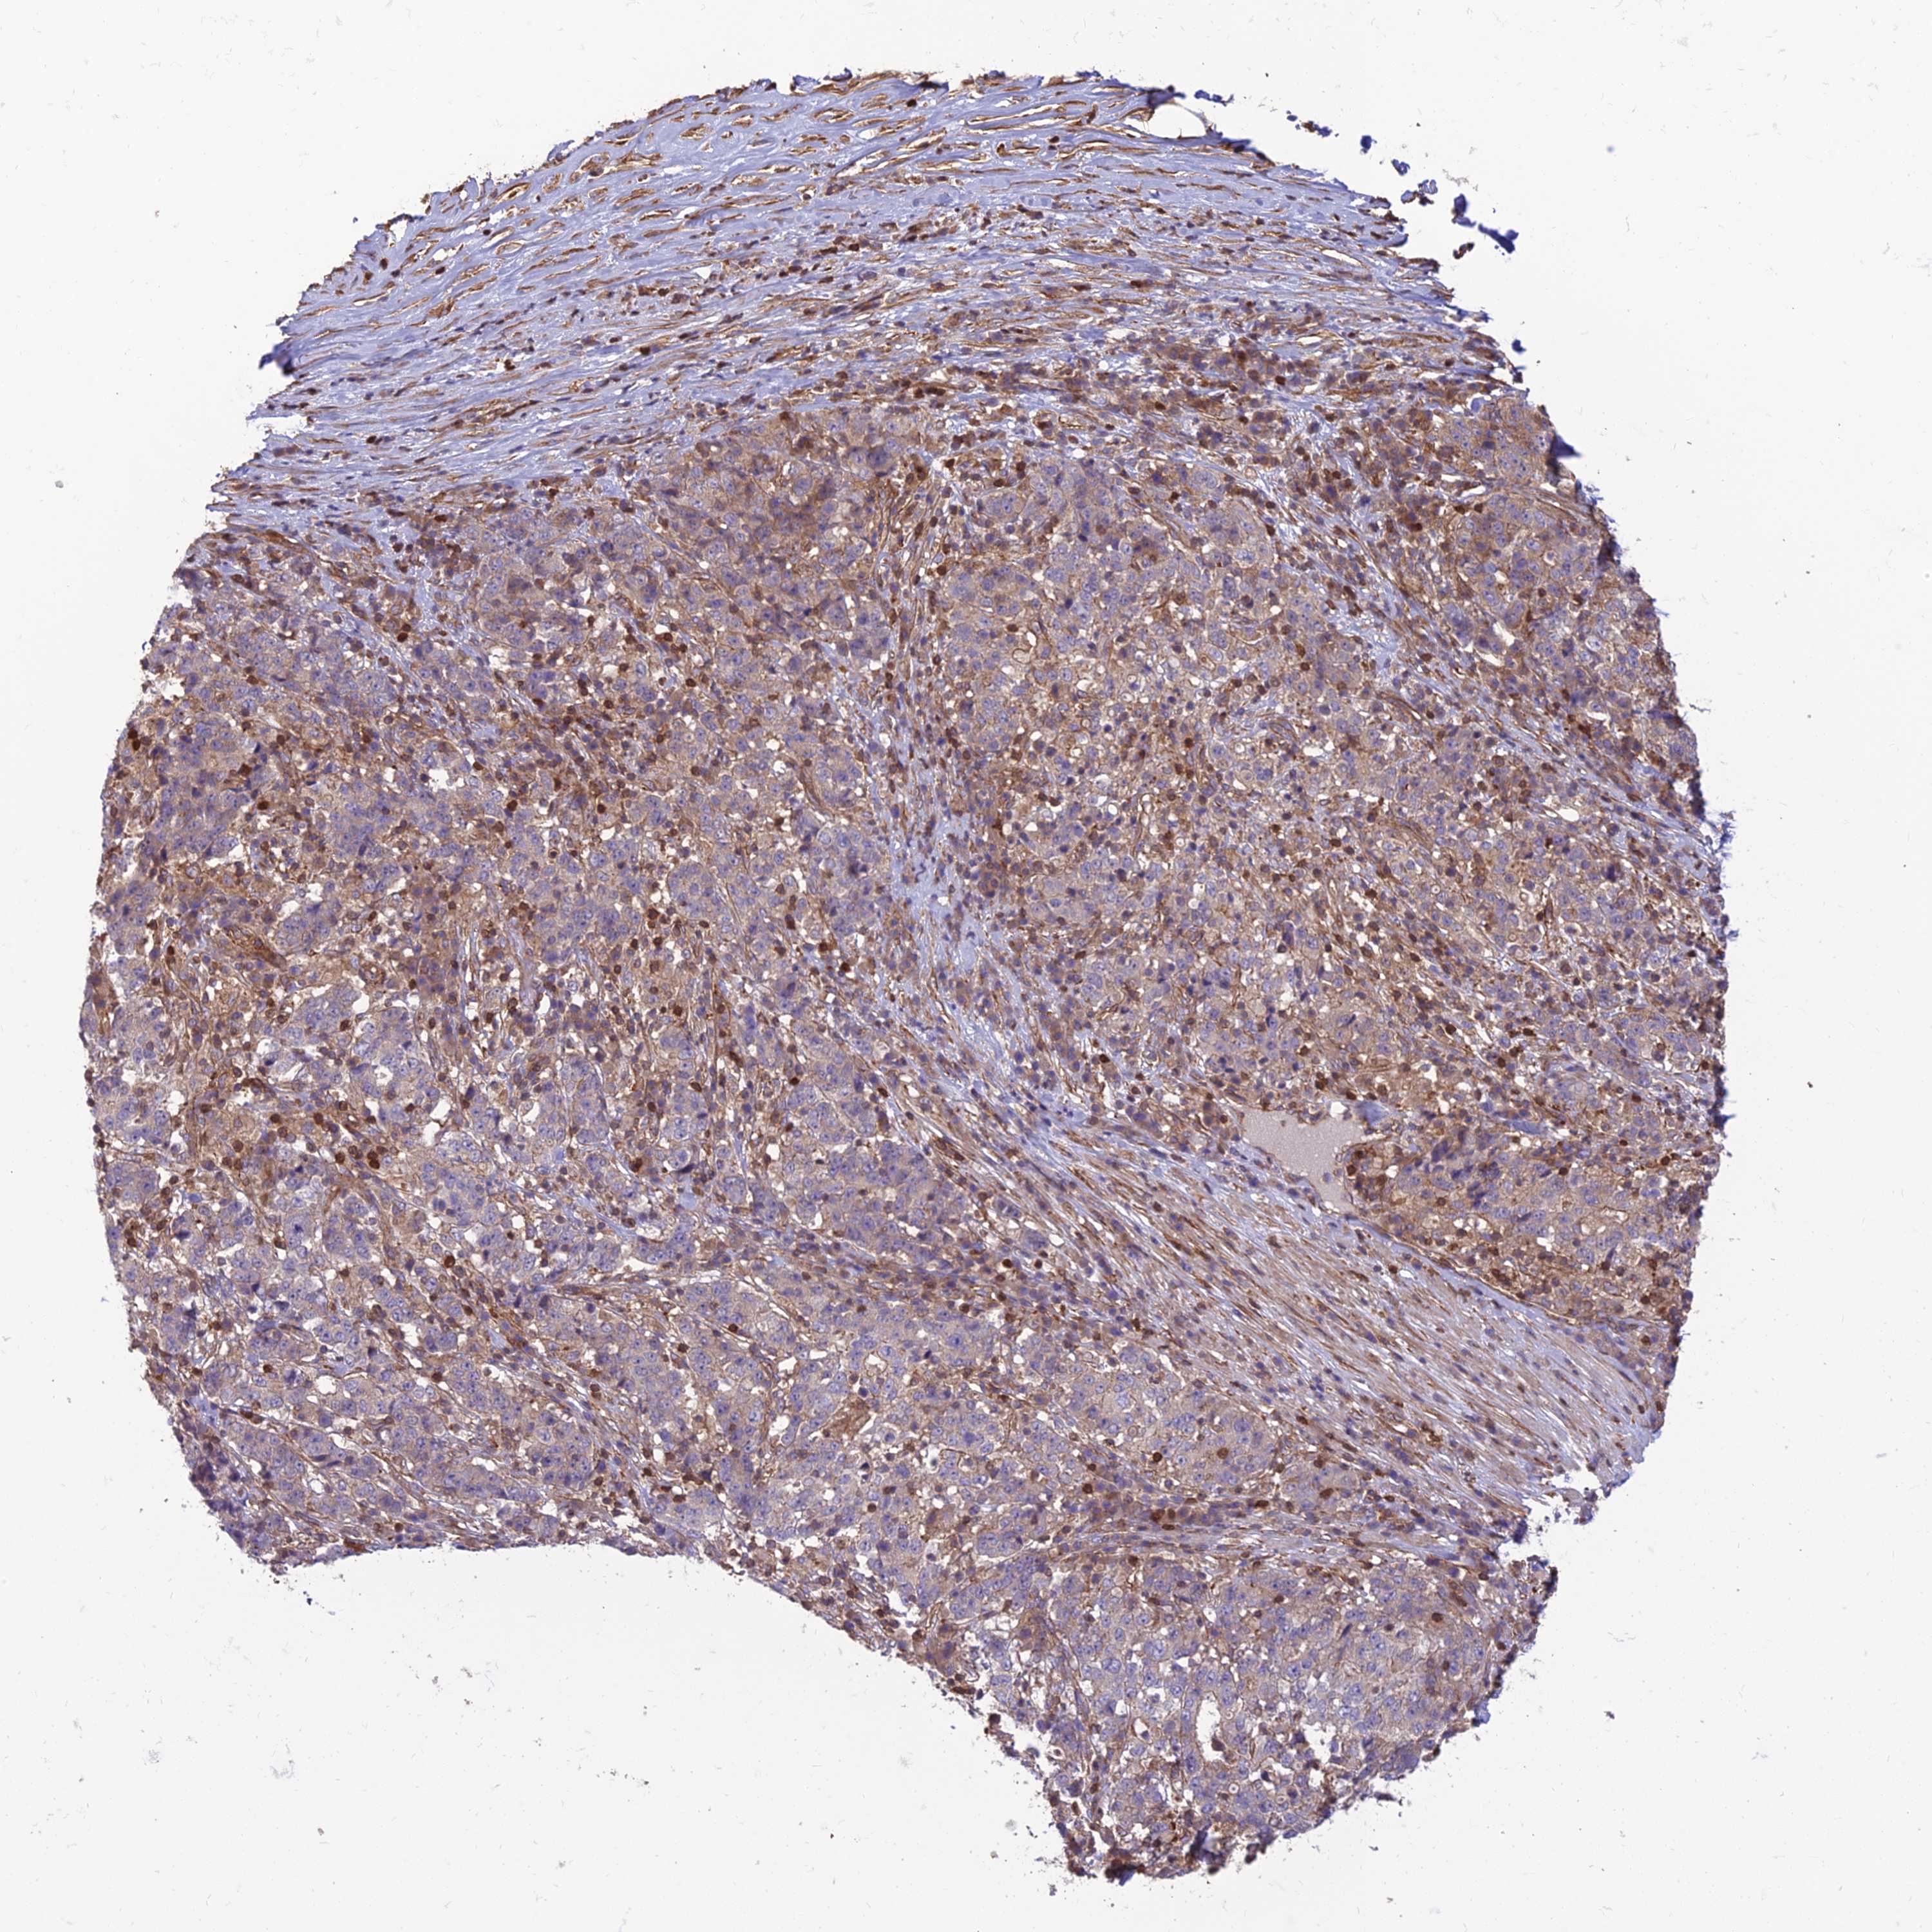

STOMACH CANCER - Protein expressioni

A mouse-over function shows sample information and annotation data. Click on an image to view it in a full screen mode. Samples can be filtered based on level of antibody staining by selecting one or several of the following categories: high, medium, low and not detected. The assay and annotation is described here.

Note that samples used for immunohistochemistry by the Human Protein Atlas do not correspond to samples in the TCGA dataset.

Antibody stainingi

Antibody staining in the annotated cell types in the current human tissue is reported as not detected, low, medium, or high, based on conventional immunohistochemistry profiling in selected tissues. This score is based on the combination of the staining intensity and fraction of stained cells.

Each image is clickable and will lead to virtual microscopy that enables deeper exploration of all samples and also displays staining intensity scores, fraction scores and subcellular localization as well as patient and tissue information for each sample.

Antibody HPA044603

Staining

High

Medium

Low

Not detected

Intensity

Strong

Moderate

Weak

Negative

Quantity

>75%

75%-25%

<25%

None

Location

Nuclear

Cytoplasmic/membranous

Cytoplasmic/membranous,nuclear

Adenocarcinoma, NOS